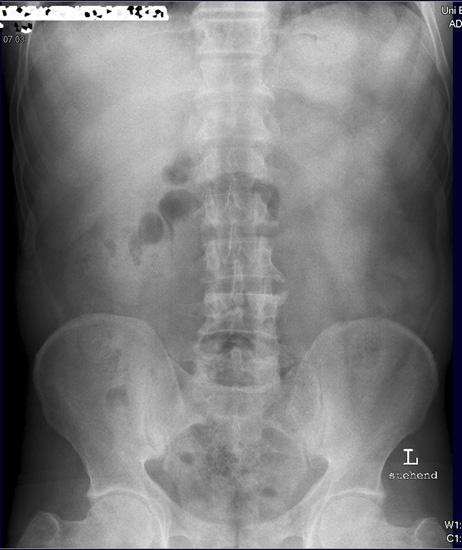

Abdomen

Abdomen im Stehen

Abdomen.jpg

Diese Aufnahme ist nicht genügend aussagekräftig, da die Zwerchfelle nicht komplett abgebildet sind. Bei Frage freie Luft sollten immer die Zwerchfelle im Stehen zu stehen sein.

Solch eine Aufnahme müsste noch mal wiederholt werden und etwas höher eingestellt werden. Viele Patienten können auf Grund ihrer abdominellen Beschwerden nicht tief genug einatmen. Deshalb nicht blind abdrücken, sondern genau zum Patienten schauen wie er einatmet, und nicht zu knapp nach oben hin einstellen.